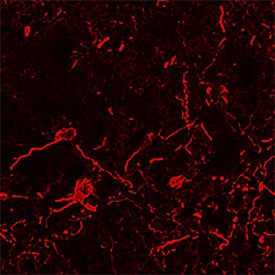

RAGE antibody in Mouse Brain by Immunohistochemistry (IHC-Fr).

RAGE in Mouse Brain.

RAGE was detected in immersion fixed frozen sections of mouse brain using Goat Anti-Mouse/Rat RAGE Antigen Affinity-purified Polyclonal Antibody (Catalog # AF1179) at 15 µg/mL overnight at 4 °C. Tissue was stained using the NorthernLights™ 557-conjugated Anti-Goat IgG Secondary Antibody (red; Catalog # NL001) and counterstained with DAPI (blue). Specific staining was localized to neurons. View our protocol for Fluorescent IHC Staining of Frozen Tissue Sections.